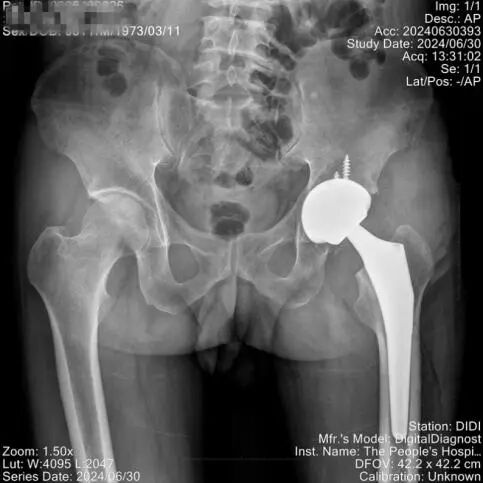

该患者左侧股骨头无菌性坏死(ARCOIV期)诊断明确,需行全髋关节置换术。经过严密的术前准备,李明全主任团队对患者实施了左侧DAA全髋关节置换手术,在麻醉科及手术室的配合下,仅用1小时就顺利完成手术,手术创伤小、术中出血少,手术切口仅9cm。

术后查体见左髋关节各方向活动均稳定,双下肢等长,麻醉消退后即可下床行走至卫生间,术后指导患者逐渐进行康复锻炼,左髋关节疼痛明显缓解,患者对手术后效果很满意,行走活动及下蹲均正常,很快重返日常生活。